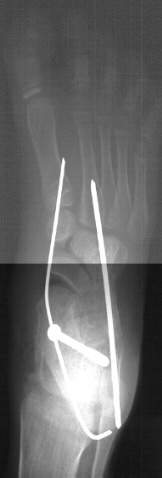

Due to persistent foot pain and excessive callus formation over the

medial arch the patient was taken to the OR and underwent surgical treatment

of the left foot. The procedure consisted of :

- subtalar arthrodesis with autograft bone graft and screw fixation

- closing wedge calcaneocuboid arthrodesis with open pinning

- reduction and open pinning of the talonavicular joint

- midfoot soft tissue release of the talonavicular, calcaneocuboid and

subtalar joints

Post operatively, the patient was placed in a long leg cast. Preliminary

results show satisfactory reduction of the talonavicular joint, correction

of hindfoot valgus, dorsiflexion of the talus on the calcaneus, and correction

of forefoot adduction immediately post op.